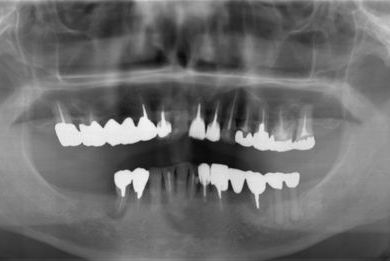

抜歯即日スピードインプラント治療+インプラント除去+セラミック治療

| 性別/年齢 | 女性 / 76歳 | ||||||||||||||||||||||||||||||||

| 主訴 | 20年前に入れたインプラントの周囲が腫れて気になっている。左下の一部治療後の歯が欠けている。 | ||||||||||||||||||||||||||||||||

| 治療内容 | インプラント5本(抜歯即日スピードインプラント)、ハイブリッドセラミック9本(セラミック用土台2本)、メタルボンドセラミック2本(メタルボンド用土台1本)、インプラント除去1本 | ||||||||||||||||||||||||||||||||